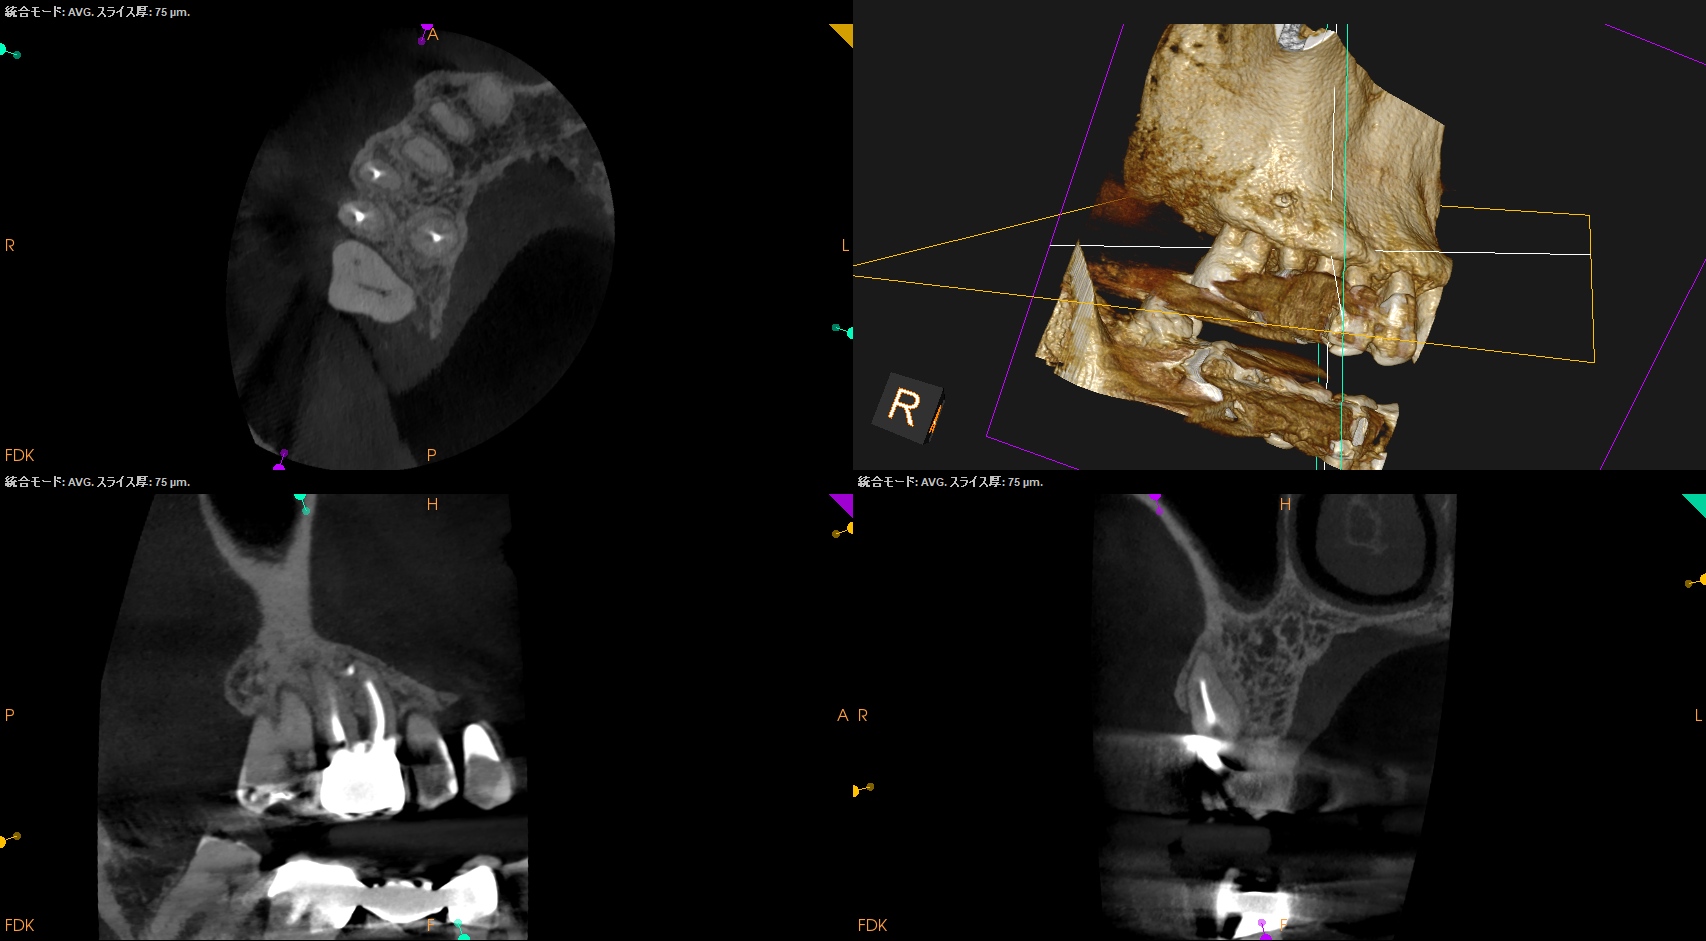

#3 RCT(2025.1.27)

PがUnderextensionの根充のような印象を与える…

が、時間が経過しないと治癒するか否かはわからない。